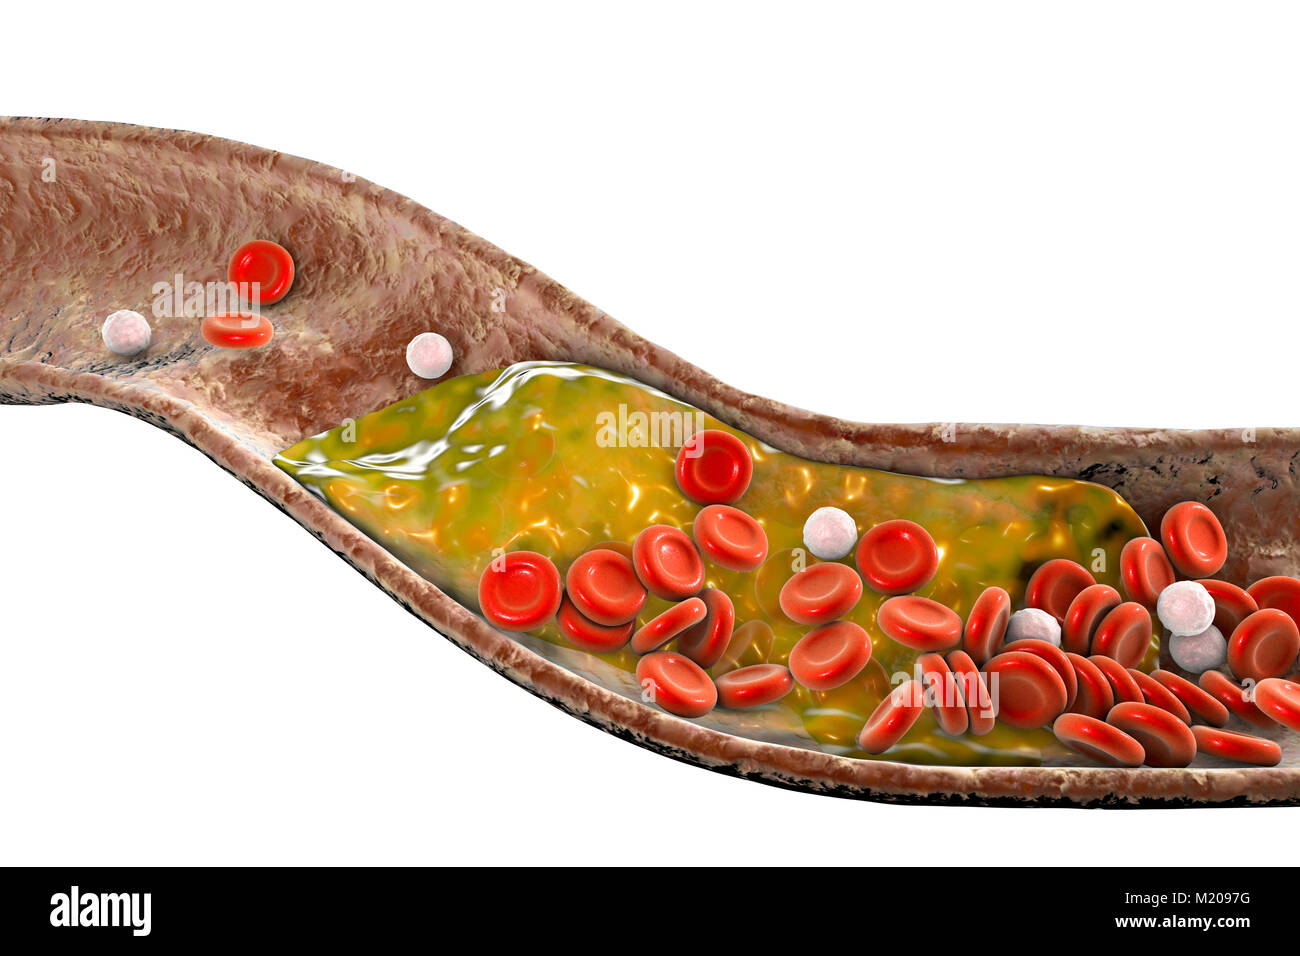

Atheromatous plaque inside blood vessel, computer illustration. A cholesterol atheroma is causing a narrowing of an artery (atherosclerosis). Stock Photohttps://www.alamy.com/image-license-details/?v=1https://www.alamy.com/stock-photo-atheromatous-plaque-inside-blood-vessel-computer-illustration-a-cholesterol-173340260.html

Atheromatous plaque inside blood vessel, computer illustration. A cholesterol atheroma is causing a narrowing of an artery (atherosclerosis). Stock Photohttps://www.alamy.com/image-license-details/?v=1https://www.alamy.com/stock-photo-atheromatous-plaque-inside-blood-vessel-computer-illustration-a-cholesterol-173340260.htmlRFM2097G–Atheromatous plaque inside blood vessel, computer illustration. A cholesterol atheroma is causing a narrowing of an artery (atherosclerosis).